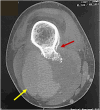

Although exostosis or osteochondroma is a common bone tumor, associated vascular complications are rare. Clinical and radiological diagnoses are sometimes challenging, and there is no codification for surgical management. We report two cases of popliteal arterial pseudoaneurysms due to osteochondroma of the distal femur. A review of the current literature about case series and case reports of patients affected by arterial pseudoaneurysm complicating osteochondroma was also performed.